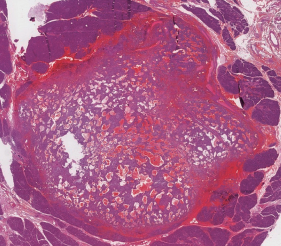

Imagen de portada

Introducción: El tumor sólido pseudopapilar del páncreas es una rara entidad que representa menos del 1% de las neoplasias pancreáticas. Suele presentarse en mujeres jóvenes y solo da síntomas de carácter compresivo una vez que alcanza un gran tamaño. Dado su comportamiento biologico incierto el tratamiento es la cirugía. Caso Clínico: Presentamos el caso de una mujer de 23 años con historia de 1 año de evolución de dolor epigástrico y baja de peso. El estudio imagenologico demostro una masa heterogenea solida-quistica dependiente de la cabeza del pancreas de aspecto neoplasico. Se realizo una biopsia incisional laparoscopica cuyo resultado fue de un tumor maligno indiferenciado, por lo que se opto por la reseccion quirurgica. Se realizó una pancreatoduodenectomía abierta sin incidentes con un post operatorio favorable. Los análisis histopatológico e inmunohistoquímico fueron compatibles con un tumor sólido pseudopapilar de páncreas.